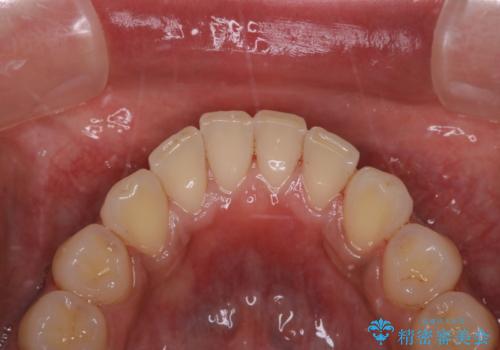

他人から口臭を指摘されて初めてのPMTC

- 他人から口臭を指摘されたので歯のクリーニング希望との事でした。

PMTC60分コースを行いました。

PMTCとはProfessinnal Mechanical Tooth Cleaning・専門器具による歯の機械的な清掃です。

バイオフィルム(細菌の塊)を破壊し、歯の表面をツルツルにすることでお口の中の細菌数を減らし歯周病のリスクが定着するのを防ぎます。更に、歯に新しい汚れがつきにくい状態になります。

PMTCを行うことにより、虫歯・歯周病・口臭予防だけでなくスッキリと爽快感が得られたり、見た目も清潔感のある状態になるため、今後の治療などお口に対するモチベーションUPにも繋がります。